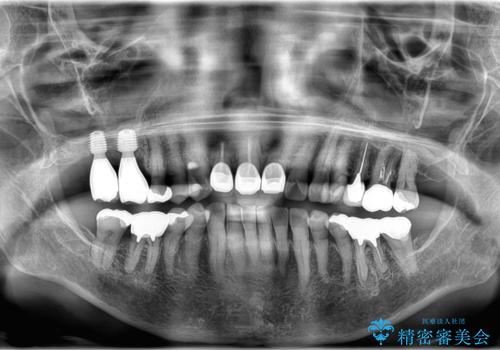

今回の治療では、まず重度歯周病の右上6番を慎重に抜歯し、その直後に6番と、すでに欠損していた7番の部分に、合わせて2本のインプラントを埋入しました。

抜歯即時埋入(6番): 抜歯と同時にインプラントを埋入することで、骨の吸収を最小限に抑え、治療期間を大幅に短縮しました。

7番のインプラント埋入: 6番と同時に埋入することで、治癒期間を一括で管理でき、効率的に治療を進めることができました。

その後、インプラントと骨がしっかりと結合するのを待ってから、最終的な被せ物(クラウン)を装着。これにより、重度歯周病で失われた2本の奥歯を、強固で安定したインプラントで再建。以前のような不安なく、しっかりと噛める快適な食生活を取り戻していただけました。